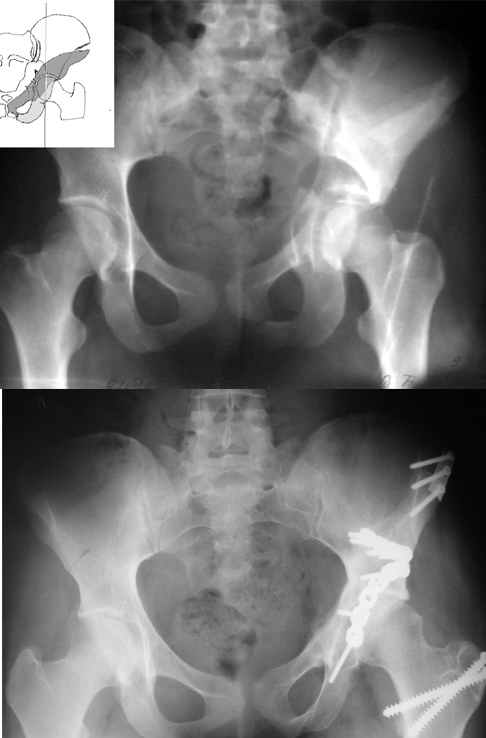

На рентгенограммах - высокий двухколонный перелом вертлужной впадины с нарушением конгруэнтности, имеется обратная клиновидность суставной щели.

Учитывая молодой возраст пациента, желательна восстановительная операция.

Доступ Y-образный чрезвертельный на здоровом боку с согнутым коленом под 90 градусов.

Сначала репонируется гребень крыла на упорной треть трубчатой пластине, затем выводится кнаружи дистальный конец перелома подвздошной кости с фиксацией трансфрактурными винтами или пластиной. Последним задняя колонна.

Лонную кость можно не трогать. Постельный режим 5-7 дней, костыли без нагрузки до 3-4 месяцев. При правильном синтезе прогноз благоприятный.